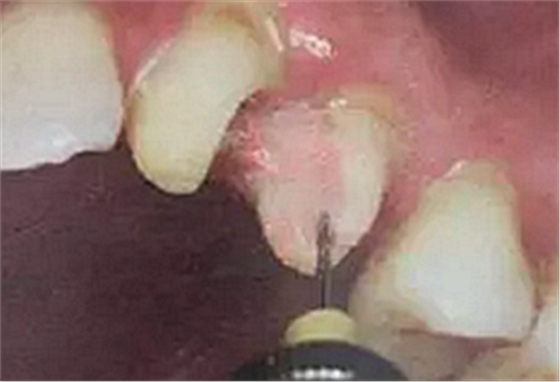

1. 沖洗預(yù)備根管

臨床多數(shù)醫(yī)生在樁道預(yù)備上習(xí)慣于干燥預(yù)備根管。

(干燥預(yù)備根管)

這樣容易破壞根管的牙本質(zhì)結(jié)構(gòu),也可形成較厚的玷污層,影響樹脂水門汀與牙體組織的粘接。

(沖洗預(yù)備根管)

應(yīng)選擇沖洗預(yù)備根管,防止牙膠及封閉劑粘連附著于根管壁形成第二層玷污層(根管治療時(shí)形成的玷污層稱為第一玷污層),利于樹脂水門汀與根管牙本質(zhì)的粘接。